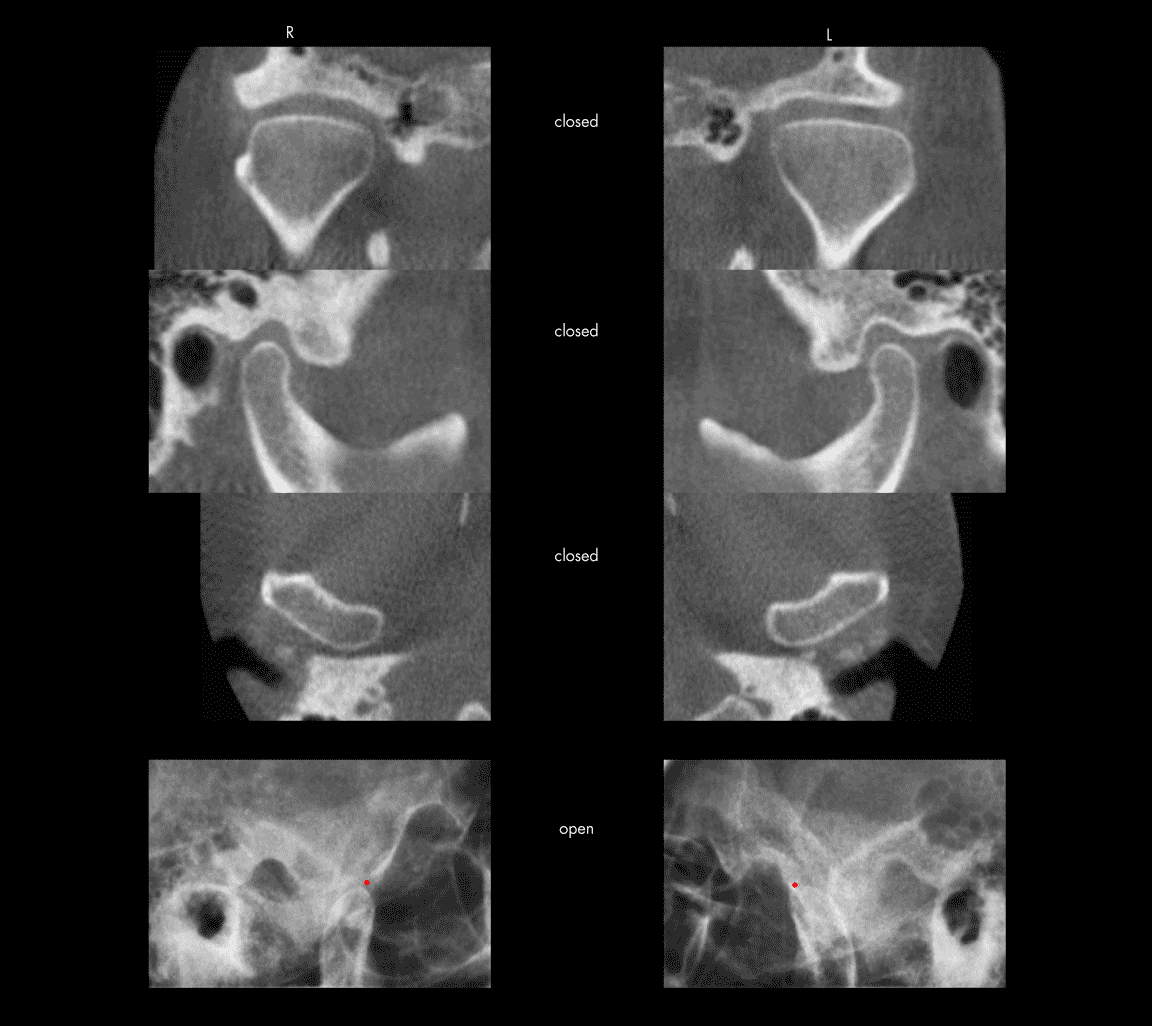

Normal temporomandibular joints